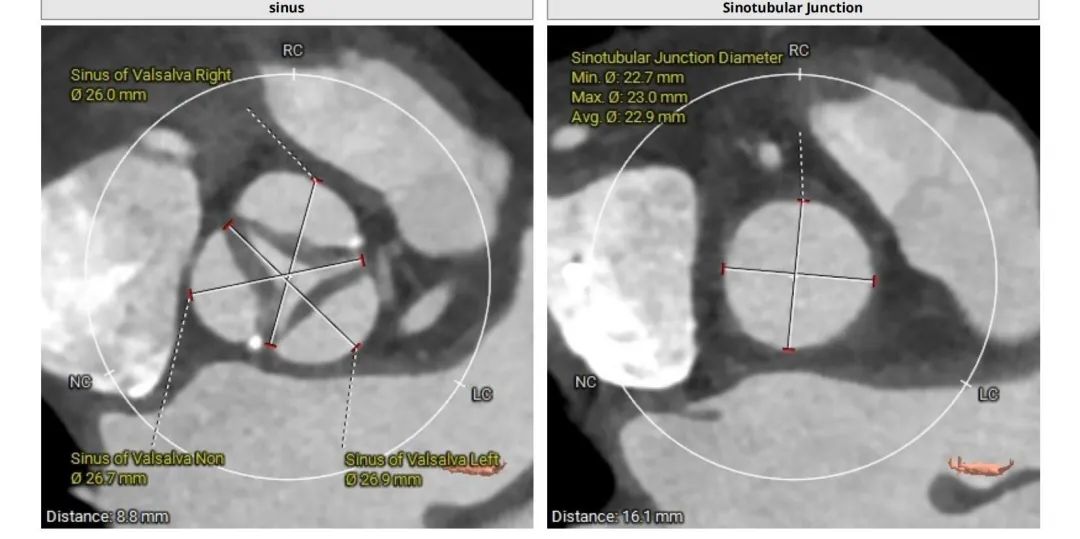

曾阿姨术前评估:法式窦结构不大;STJ:高度16.1mm,直径22.9mm

姚启恒教授介绍说:“术前评估患者瓣叶明显增厚,左右冠窦部分粘连,法式窦结构不大。术中左冠开口闭塞高风险,团队预先行冠脉保护,主动脉弓降部走行接近直角,过弓可能遇到其他意外困难,很考验术中精准操作。”